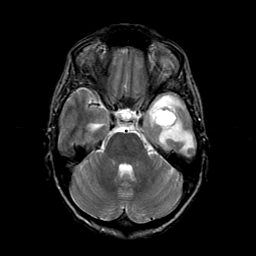

Metastatic bronchogenic carcinoma: T2-weighted MR -- Slice #6

[Home][Help][Clinical] Slice 6